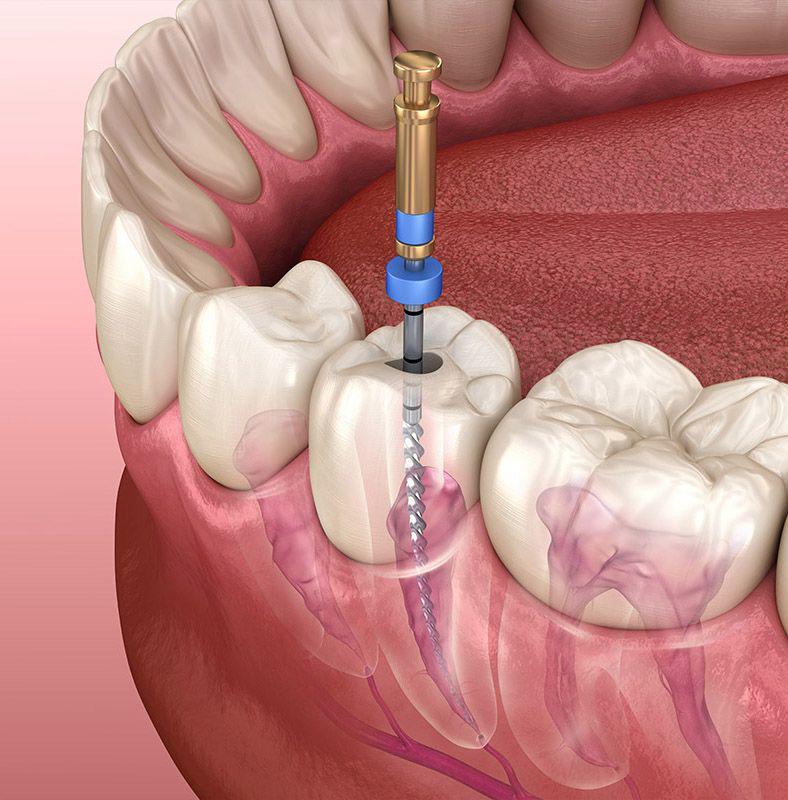

1. Accesul și pregătirea canalului

Se creează acces către nerv și se modelează canalele

Tehnici: manuale, rotative sau combinate

Scop: curățarea eficientă fără a slăbi rădăcina

2. „Scoaterea nervului” și dezinfecția

Se elimină țesutul infectat și bacteriile ascunse

Se folosesc soluții speciale care curăță și dezinfectează fiecare canal